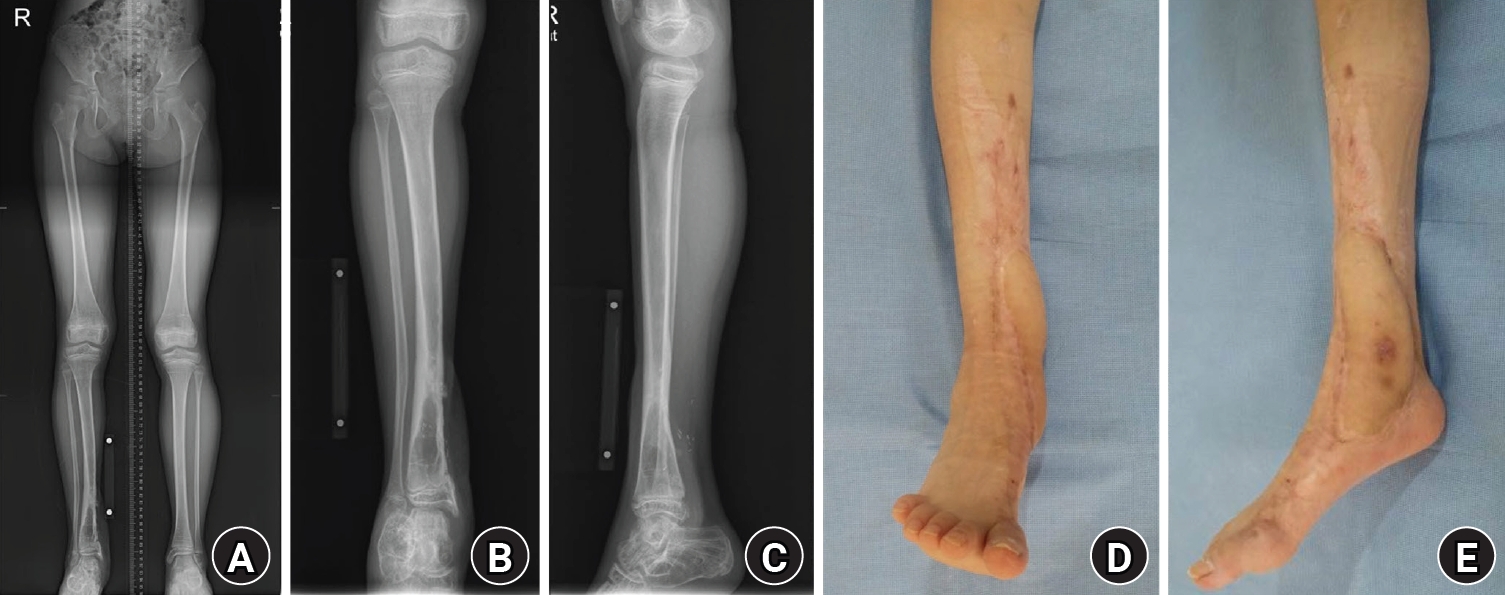

The patient underwent irrigation and debridement with temporary stabilization using an external fixator (Fig. 2). Serial irrigation and debridement procedures (marginal debridement) were performed as needed until the wound condition allowed definitive reconstruction.

Fig. 2.

Postdamage control stabilization with external fixation. (A) Anteroposterior gross photograph obtained after initial irrigation and debridement, showing temporary stabilization with an external fixator. (B) Lateral gross photograph obtained after initial irrigation and debridement, demonstrating temporary stabilization with an external fixator. (C) Anteroposterior radiograph obtained after initial irrigation and debridement, showing temporary stabilization with an external fixator. (D) Lateral radiograph obtained after initial irrigation and debridement, demonstrating temporary stabilization with an external fixator.

Fig. 2. Postdamage control stabilization with external fixation. (A) Anteroposterior gross photograph obtained after initial irrigation and debridement, showing temporary stabilization with an external fixator. (B) Lateral gross photograph obtained after initial irrigation and debridement, demonstrating temporary stabilization with an external fixator. (C) Anteroposterior radiograph obtained after initial irrigation and debridement, showing temporary stabilization with an external fixator. (D) Lateral radiograph obtained after initial irrigation and debridement, demonstrating temporary stabilization with an external fixator.